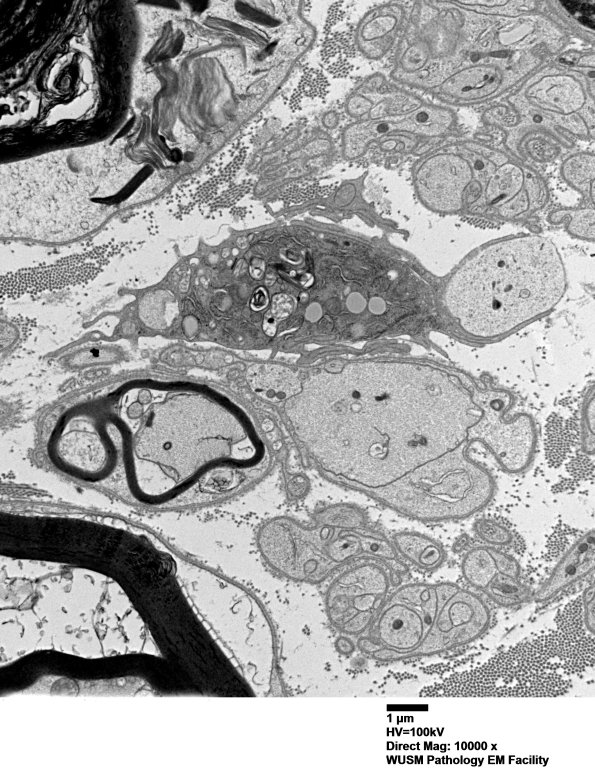

4F10A,B A macrophage with cytoplasmic myelin debris extending pseudopods around a naked axon. (electron micrographs)